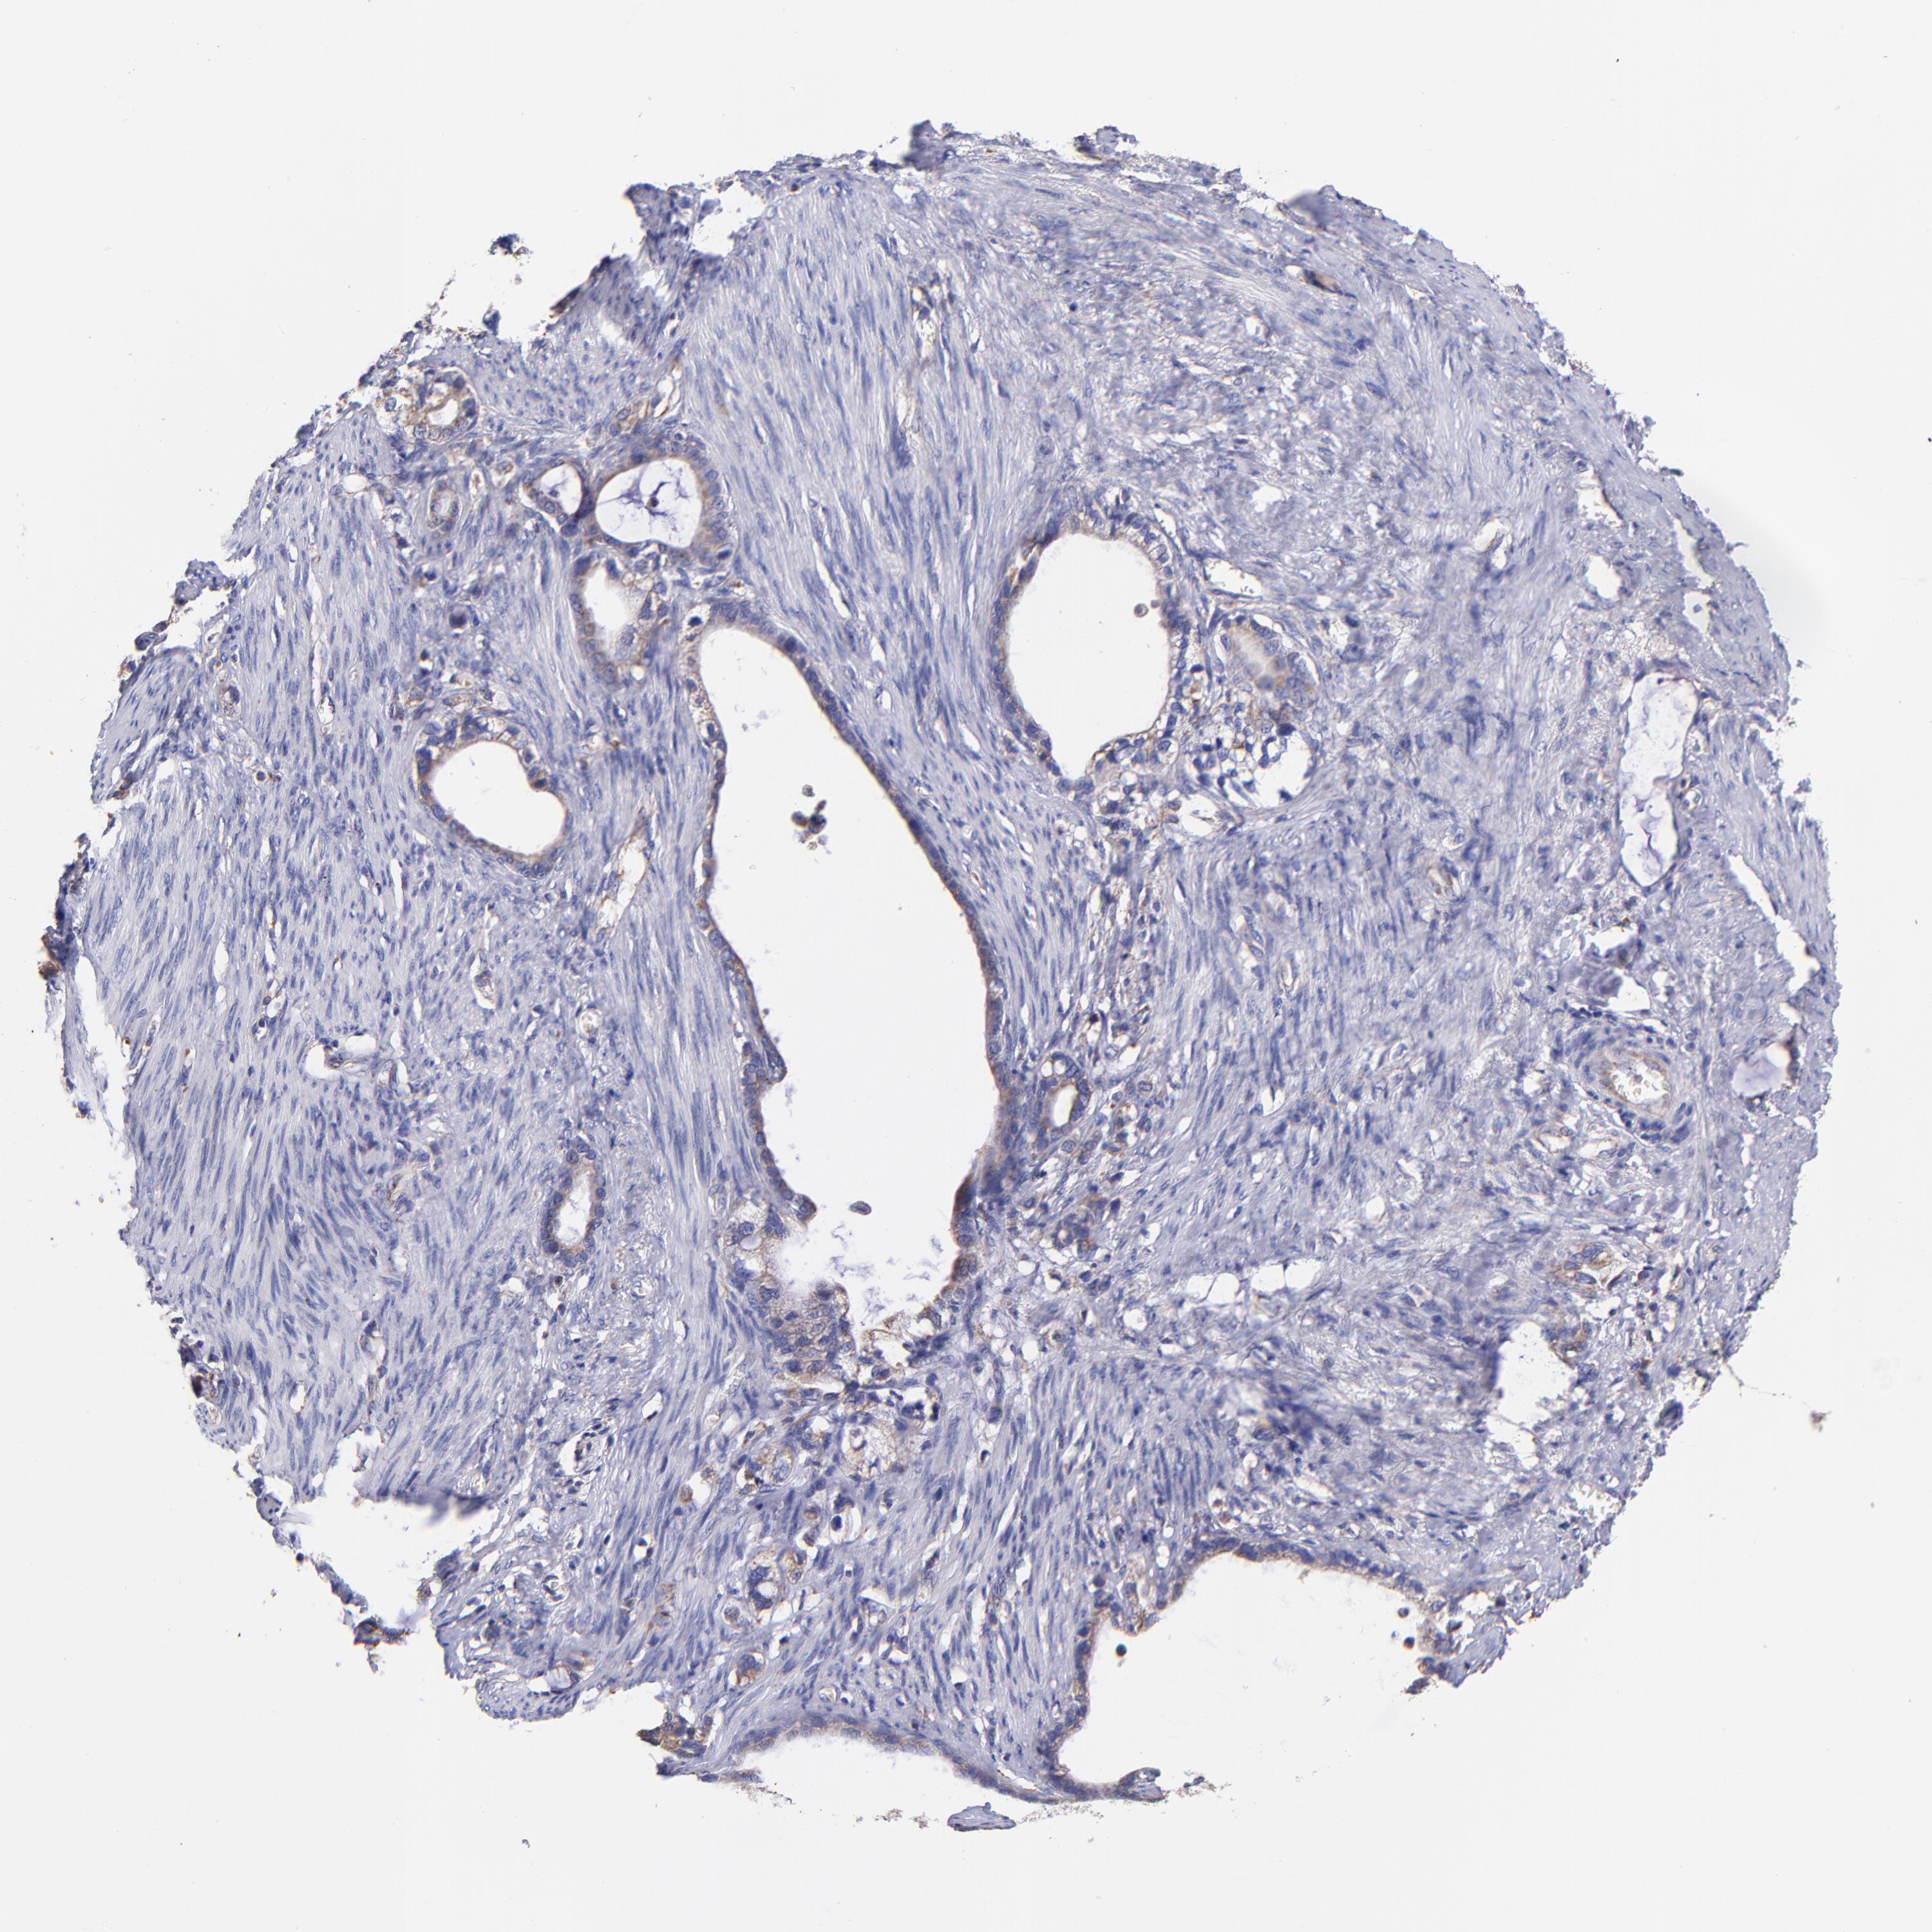

STOMACH CANCER - Protein expressioni

A mouse-over function shows sample information and annotation data. Click on an image to view it in a full screen mode. Samples can be filtered based on level of antibody staining by selecting one or several of the following categories: high, medium, low and not detected. The assay and annotation is described here.

Note that samples used for immunohistochemistry by the Human Protein Atlas do not correspond to samples in the TCGA dataset.

Antibody stainingi

Antibody staining in the annotated cell types in the current human tissue is reported as not detected, low, medium, or high, based on conventional immunohistochemistry profiling in selected tissues. This score is based on the combination of the staining intensity and fraction of stained cells.

Each image is clickable and will lead to virtual microscopy that enables deeper exploration of all samples and also displays staining intensity scores, fraction scores and subcellular localization as well as patient and tissue information for each sample.

Antibody HPA001927

Staining

High

Medium

Low

Not detected

Intensity

Strong

Moderate

Weak

Negative

Quantity

>75%

75%-25%

<25%

None

Location

Nuclear

Cytoplasmic/membranous

Cytoplasmic/membranous,nuclear

Adenocarcinoma, NOS